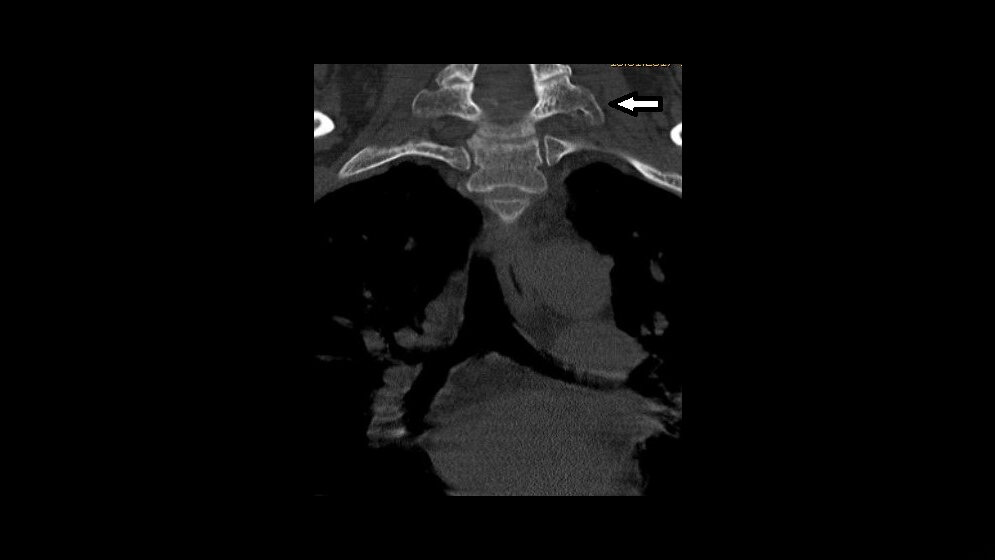

Die Inzidenz der zahlenmäßig varianten Rippenanlagen beträgt 6,3 %. Bei isoliertem Vorkommen handelt es sich um Normvarianten. Zervikale Rippen kommen bei etwa 2 % der Population vor. Sie sind in der Differenzialdiagnose bei supraklavikulären Raumforderungen zu berücksichtigen.

The incidence of abnormal number of ribs in the normal popula-tion is 6.3 %. When isolated, this finding is a normal variant. The prevalence of cervical ribs is 2 % of patients. Differential diagnosis of a supraclavicular mass includes cervical ribs.